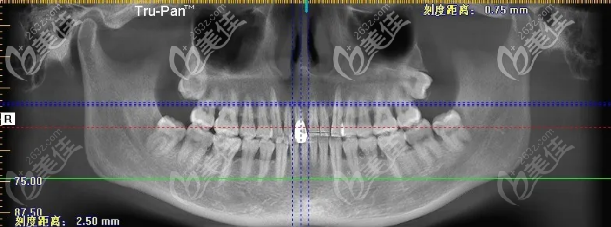

而且医生还查出,我松动的门牙处还患有根尖炎,更是没有办法用了,所以索性做了即刻种植,我当时选的是Nobel Active 3.5 X 15mm种植体,我还植入了少量的骨粉,因为医生说种植体与我的骨板间有2MM的间隙。

(这是我当时拍的片子)